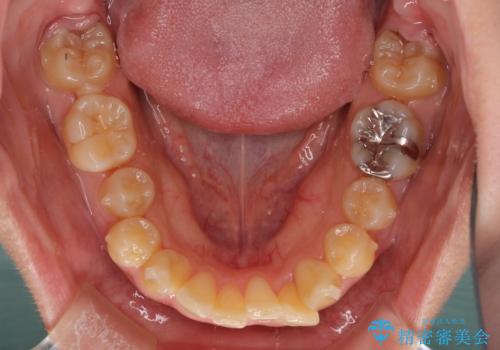

八重歯の抜歯矯正 補助装置を用いたインビザライン矯正

来院当初、上顎の八重歯は気にしていらっしゃらなかったのですが、矯正治療をするのであれば、しっかりと治した方が良いと説明し、全顎矯正を行うこととしました。

八重歯の移動量が多く、インビザライン単体での治療は困難と判断し、補助装置により八重歯移動後にインビザラインを用いることとしました。

装着時間をしっかりと守ってくださったので、予定通りの期間で終了することができました。